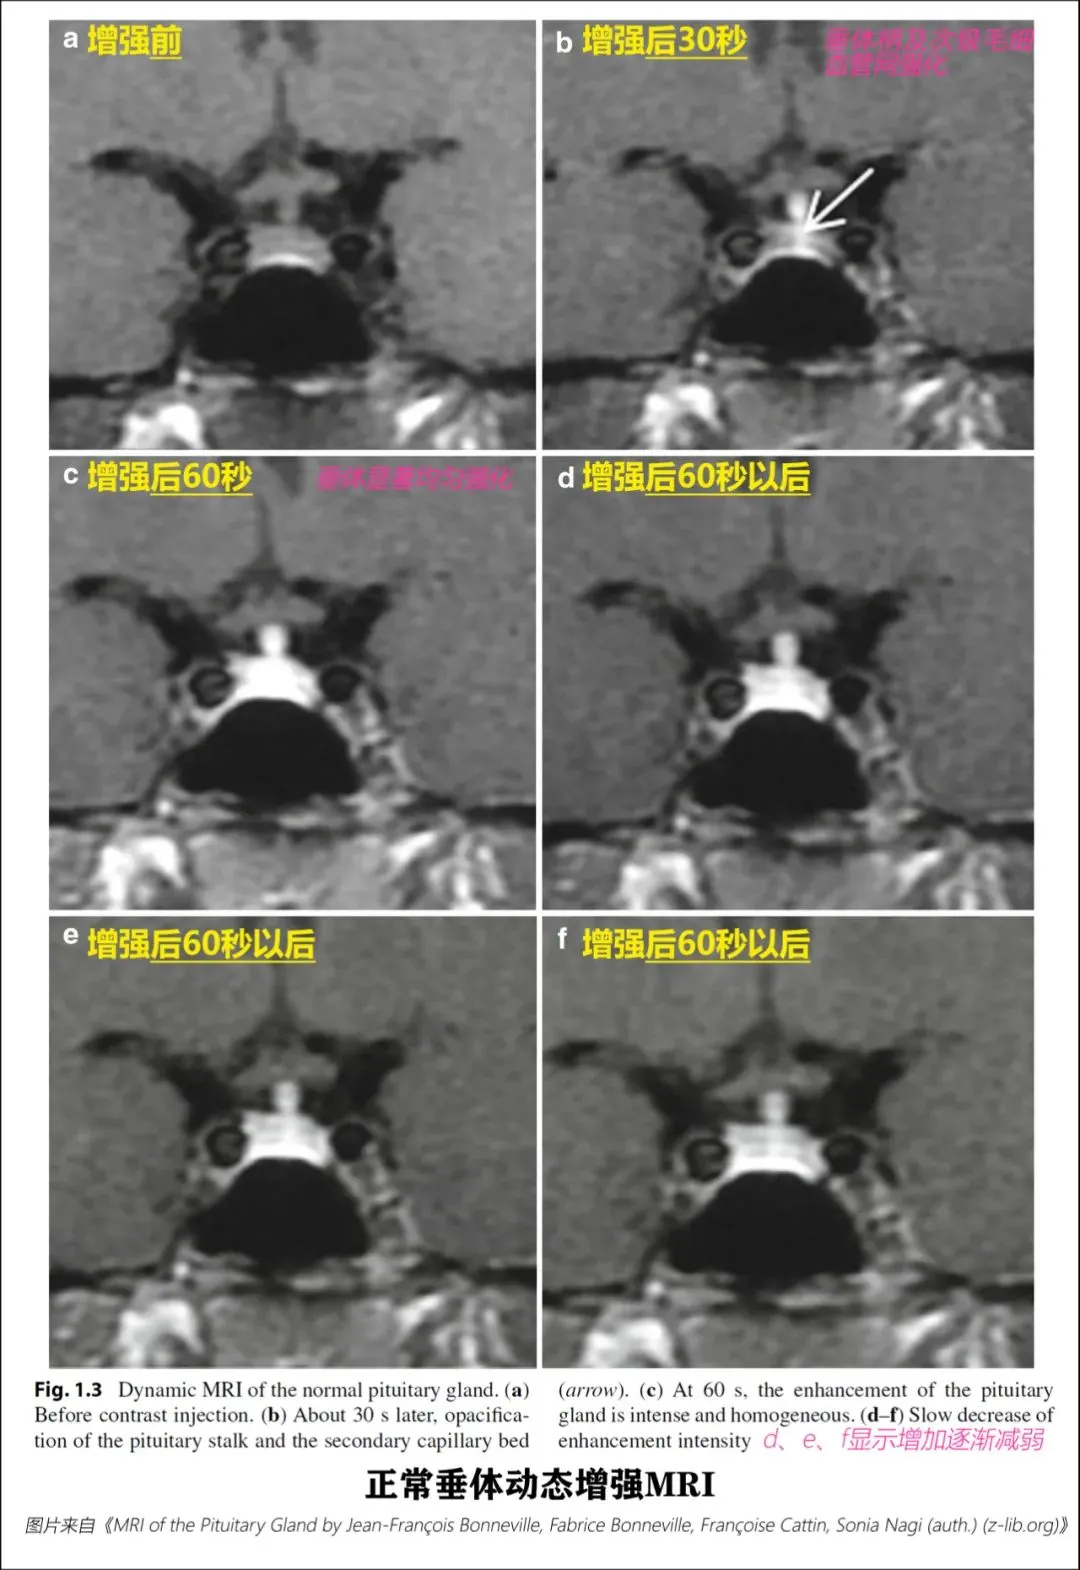

3. DCE MRI

动态增强磁共振成像(Dynamiccontrast-enhanced magnetic resonance imaging)

DCEMRI是诊断垂体微腺瘤的准确方法

垂体前叶主要由门脉供血,动态成像上,前叶强化晚于后叶。

注射轧对比剂后20-30秒:垂体柄及垂体上部强化。

注射轧对比剂后40-60秒:垂体显著强化,之后信号缓慢下降。